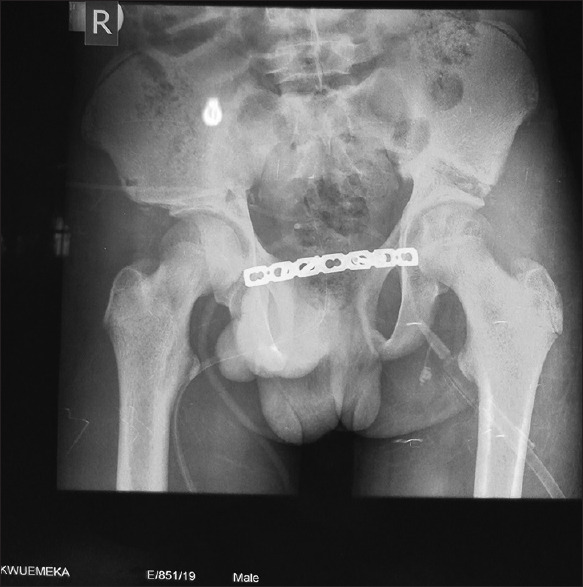

Postoperatively, he had bilateral skin traction, broad-spectrum antibiotics, anticoagulants and was commenced on isometric muscle exercise of the lower limbs. A check X-ray done after surgery showed good bone-fragment alignment for healing and an intact plate and screws [Figure 4]. He had superficial incisional surgical site infection of the abdominal wound with partial wound breakdown which was managed with wound dressing. The ureteric stents were removed on the 18 day after surgery. The urethral stent/drain was removed on the 21 day after surgery, while the supra-pubic stent was spigotted. He had the urge to urinate and voluntarily urinated, however had dribbling of urine in between. There was the slow progressive improvement of urine dribbling. He was placed on Kiegel’s exercise to help improve the urinary sphincteric action. There was also a vesico-cutaneous fistula (distal to the site of suprapubic cystostomy) that healed spontaneously with prolonged suprapubic bladder drainage. At 6 weeks after surgery, a repeat pelvic X-ray showed a substantial union to allow for mobilisation. The suprapubic drain was removed by the 7th-week post-surgery. He was discharged home on the 58th day after surgery, with persisting urinary frequency and dribbling of urine, but a very happy and vibrant person. There was no limb length disparity.

Figure 4.

Post-surgical pelvic xray showing osteotomy sites and the plating

Early repair makes correction of bony anomaly easy. Closure of the pubic diastasis is only possible with osteotomy. There is no possibility of apposing the pubis without osteotomy as is done in some neonatal cases. The osteotomy done was a bilateral anterior iliac osteotomy, which is commonly used in late-presenting bladder exstrophy repairs.[8] The osteotomy was quite challenging at this age vis-à-vis the greater force required to break the bones with its attendant risk of injury to pelvic viscera. The blood loss was also substantial, and the conventional means to stabilising the bones could not suffice.[8] The stabilisation was with a 7-hole plate and screw, leaving the middle three holes unscrewed, bilaterally. Shoukry and Shoukry[10] in their series of repair of classic bladder exstrophy in five adults did not use pelvic osteotomies. They did make mention of pubic approximation. However, they have to achieve abdominal wall closure by fasciocutaneous M-plasty.[10]